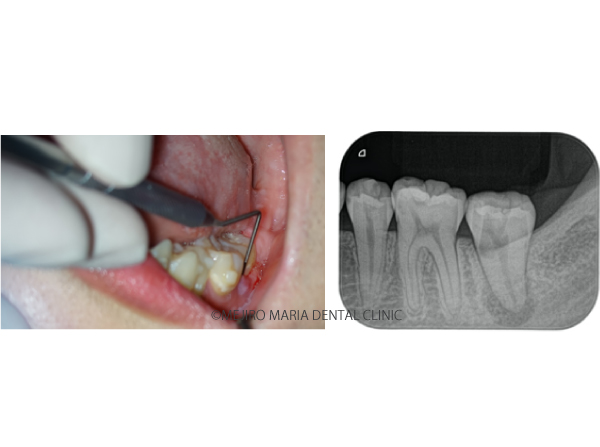

当院での初診時の検査でレントゲンを確認すると、歯冠(歯肉の上に出ている歯の部分)に人工的な透過像が確認でき、前医での治療の際に、偶発的に歯に穴(穿孔・パーフォレーション)が開けられてしまったことが予想できました。また、歯肉(歯ぐき)が大きく腫れあがり、限局的な歯周ポケットが確認される上に、穴のあいている部分と歯周ポケットが交通している可能性も考えられるなど、状況は複雑化していました。

今回の患者様は、左下の歯の痛みを訴え他院を受診しましたが、治療直後から痛みがひどくなったことで当院に来院されました。当院での診査時には、歯ぐきの腫脹、ならびに歯の一部分に限局的な歯周病ポケットが確認され、歯内歯周病変(※)にも罹患していました。さらに、穿孔(パーフォレーション・歯に穴があいてしまっている状態)の可能性があることから、状況が複雑化(コンプロマイズド)しており、適切な順番で処置を行うことが重要でした。